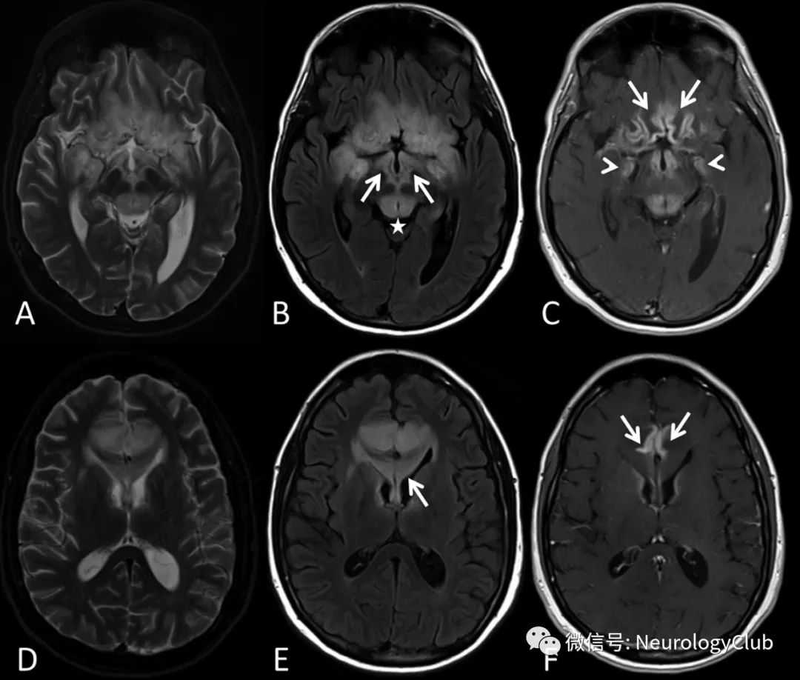

腦炎,不可忽視的年輕殺手